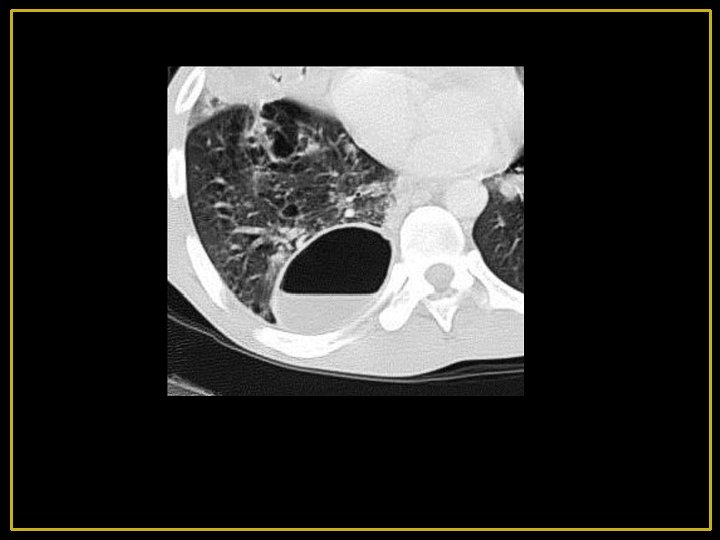

Embolie septique - Secondaire à une dissémination hématogène - ++ endocardite droite ou thrombophlébite septique Nodules alvéolaires multiples, épars et bilatéraux de contours mal définis prédominant aux niveau des bases et en périphérie frb(h ,

Maladie de Wegener - Vascularite granulomateuse - Atteinte pulmonaire isolée ou associée à une atteinte ORL et rénale - L’atteinte pulmonaire peut être subaiguë ou chronique - Nodules à limites floues, de taille variable le plus souvent excavés volontiers migratrices - Parois épaisses et irrégulières - Régression des lésions sous traitement